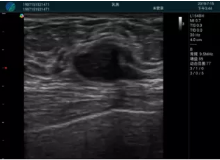

腺體內(nèi)部清晰顯示一低回聲塊影,形態(tài)不規(guī)則,邊界模糊,邊緣呈毛刺狀,內(nèi)部見砂礫樣鈣化